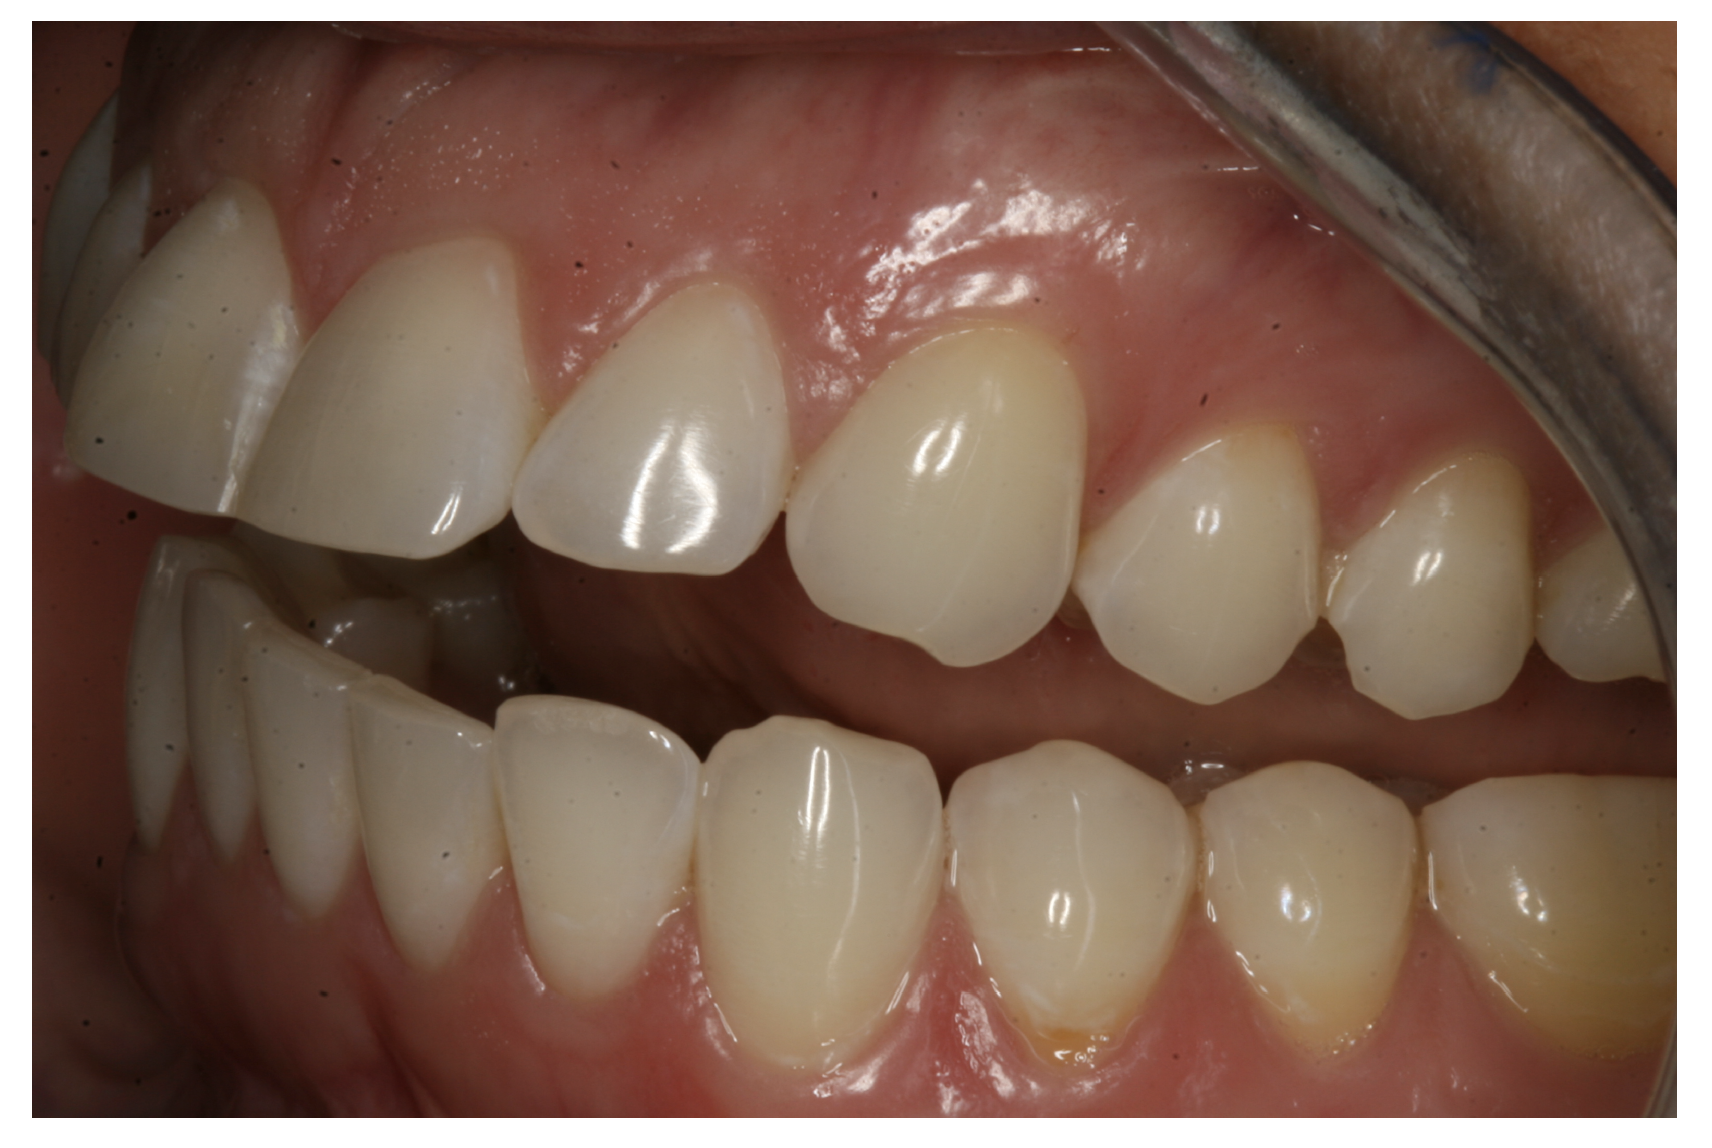

For the case in Figure 9 through Figure 11, the patent presented for an initial consultation with bonding completed on teeth Nos. 7 through 10 a few years prior with a chief complaint of not liking the way the resin bonding looked and how it was wearing. Up to this point, the bonding had repeatedly chipped and been repaired three times already. The patient's canines also exhibited signs of incised wear and flattening, which she did not like. Based on the patient's goals for her smile and her financial budget, she elected to have porcelain veneers completed on teeth Nos. 6 through 11. The total esthetics of the case design were somewhat limited given that the patient's esthetic zone included her posterior teeth and mandibular anterior teeth. Therefore, the color and characteristics of the veneers had to match her existing dentition closely.